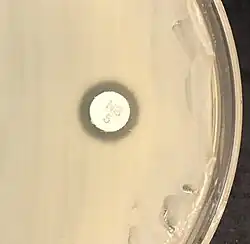

| S. saprophyticus on Mueller–Hinton agar exhibiting resistance to novobiocin characteristic for species identification | |

Staphylococcus saprophyticus is identified as belonging to the genus Staphylococcus using the Gram stain and catalase test. It is identitified as a species of coagulase-negative staphylococci (CoNS) using the coagulase test. Lastly, S. saprophyticus is differentiated from S. epidermidis, another species of pathogenic CoNS, by testing for susceptibility to the antibiotic novobiocin. S. saprophyticus is novobiocin-resistant, whereas S. epidermidis is novobiocin-sensitive.[3]